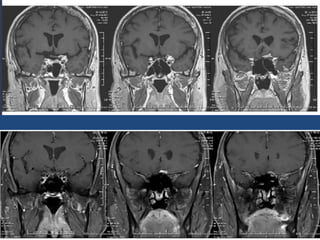

#Germinoma

• 5-25 yrs

• AKA dysgeminoma, intracranail seminoma

• MC at stalk and hypothalamus and pineal

region

• Crawls along floor of the 3rd vent

• Ddx: LCH, craniopharyngioma

• Adult: sarcoid, lymphoma